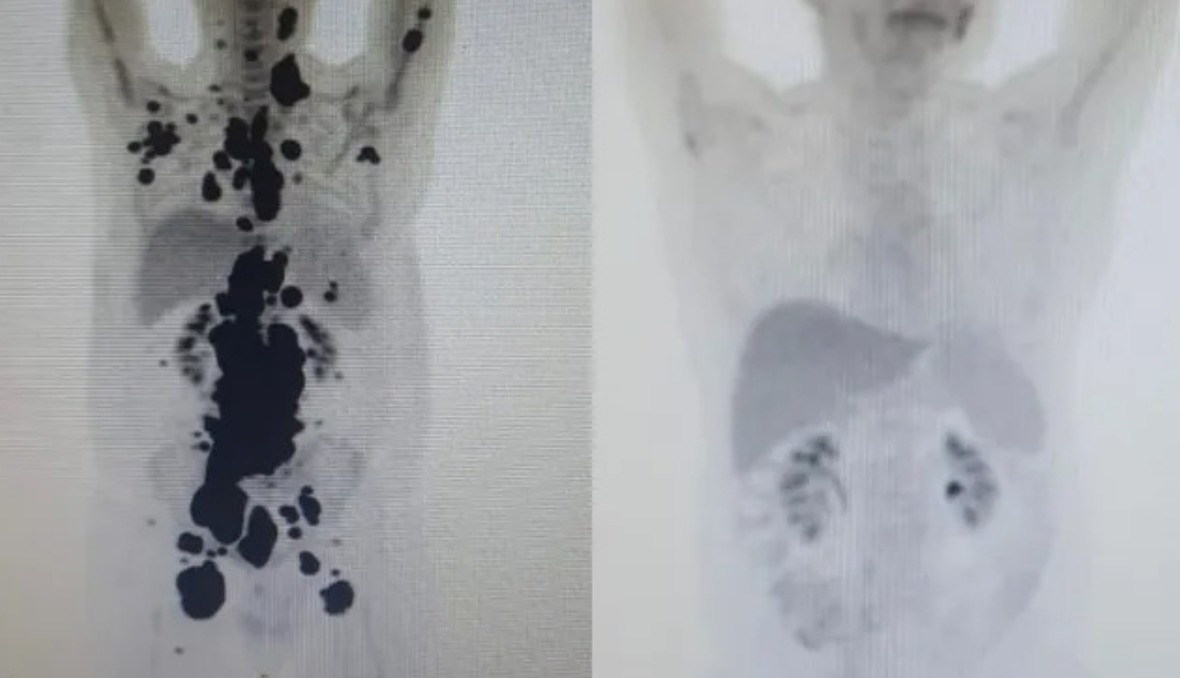

Neste ano, para marcar a data especial de um ano livre da doença, Paulo realizou um novo Pet Scan no dia 22 de abril. O exame, que utiliza um contraste especial para detectar células cancerígenas, não apresentou nenhum sinal da doença. O resultado, recebido na sexta-feira (3), coincidiu com o aniversário do Dr. Carlos Maurício, o médico que o acompanhou durante todo o processo.